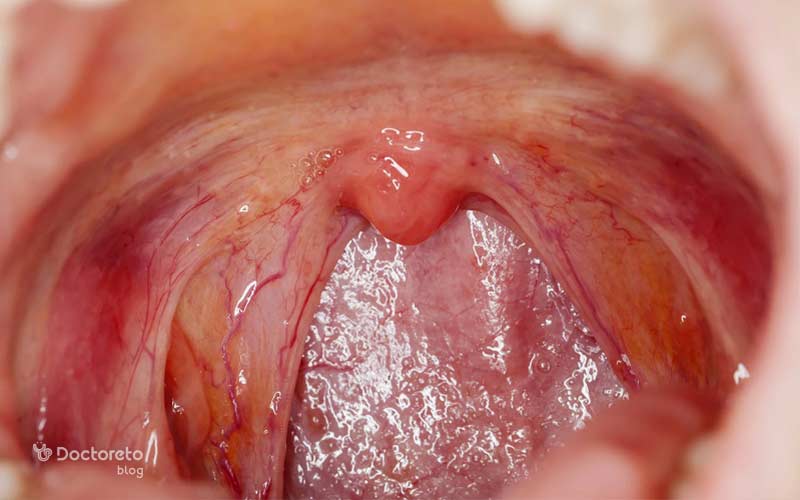

عکس لوزه طبیعی و سالم

لوزههای سالم معمولاً صورتیرنگ هستند و سطحی یکنواخت دارند. در حالت طبیعی، لوزه ها از کنارههای گلو بیرون نزده و فقط کمی قابل مشاهده هستند. زمانی که لوزهها دچار عفونت یا التهاب میشوند، معمولاً قرمز و متورم به نظر میرسند.